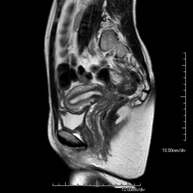

Prova diagnòstica no invasiva que consisteix en l'obtenció d'imatges d'alta definició anatòmica de la pelvis mitjançant l'ús d'un camp electromagnètic i ones de ràdio (amb un emissor i un receptor). No utilitza radiació ionitzant. Es realitza per a l'estudi de patologies d'úter, d'ovari, de trompes i de vagina, ja siguin d'origen tumoral, inflamatori o vascular. També permet valorar les estructures adjacents localitzades a la pelvis i la identificació de les seves alteracions. De vegades és necessari l'ús de contrast intravenós (Gadolini) per caracteritzar les lesions. - RM Pelvis masculina

Prova diagnòstica no invasiva que consisteix en l'obtenció d'imatges d'alta definició anatòmica de la pelvis masculina mitjançant l'ús d'un camp electromagnètic i ones de ràdio (amb un emissor i un receptor). No utilitza radiació ionitzant. No requereix preparació prèvia. En algunes ocasions necessita l'ús de contrast paramagnètic (Gadolini) per caracteritzar les lesions. Aquesta prova permet valorar òrgans com la bufeta urinària, la unió entre els urèters i la bufeta, la pròstata, les vesícules seminals, la uretra i els ossos de la pelvis, entre d'altres. - RM de Fetge